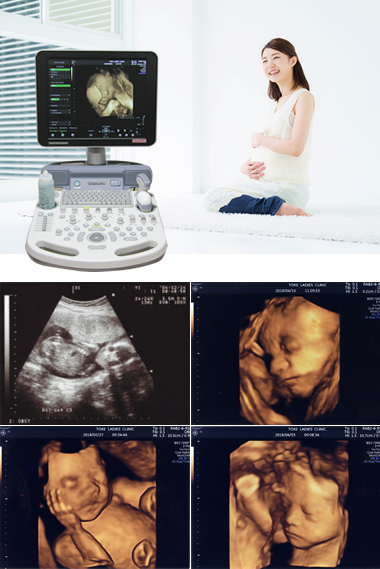

- 妊娠初期の5・6週から、胎児心臓の鼓動をモニターで見られます。

- 各回の健診時の、超音波映像(エコー画像)の録画が可能です。

- 当クリニックでは、4D超音波診断装置を導入しており、主に妊娠16~24週の間にて、検査を行っています。

妊婦健診日外で行っておりますので、受付にて検査の予約をお願いします。

当クリニックでは、女性の気持ちに配慮した内診台を採用しております。 また、赤ちゃんの心臓の鼓動をモニターで見たり、超音波映像(エコー画像)、4D超音波診断装置による動画の録画も可能です。